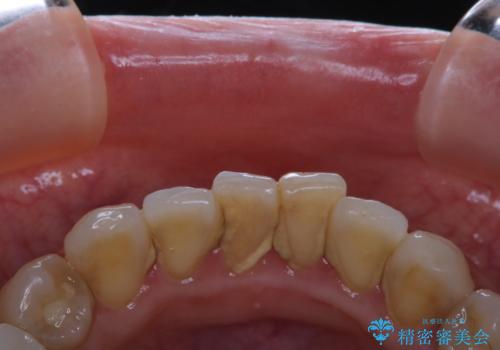

磨けているようで磨けていない汚れをPMTCで徹底的に除去